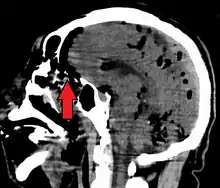

Pneumocephalus and comminuted fracture of the frontal sinus